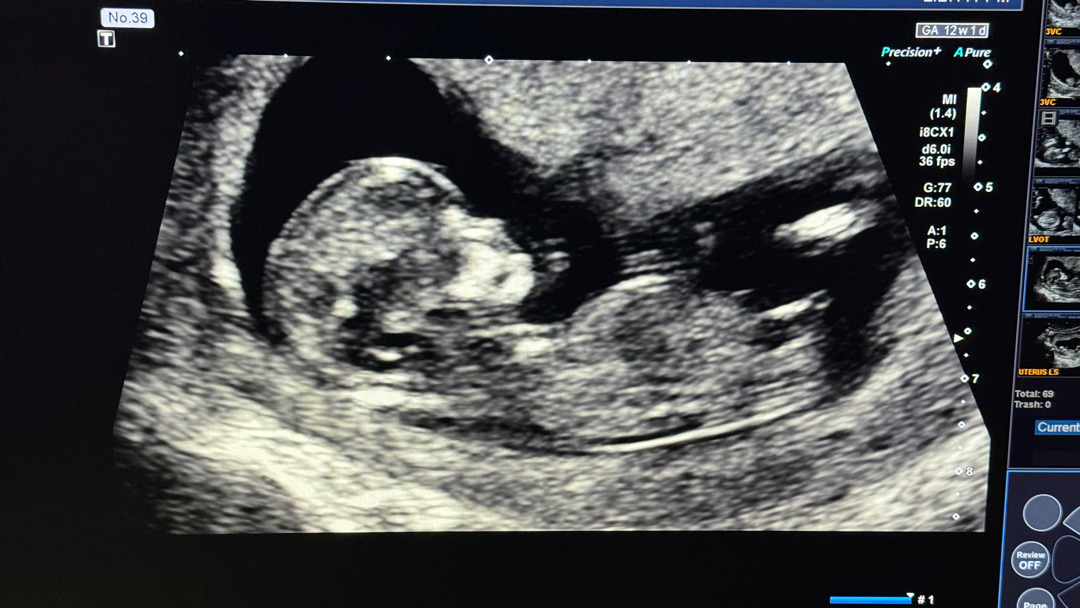

12์ฃผ 1 ์ฐจ ์ฌ์ง ๐

์๋ ํ์ธ์ ํธ์ฃผ ๊ฑฐ์ฃผ์ค์ธ ์๋น ์๋ง์ ๋๋ค ๐ 12์ฃผ 1 ์ผ์ฐจ์ ์ฌ์ฅ์๋ฆฌ๋ฅผ ์ฒ์ ๋ค์์ด์ ์ผ๋ง๋ ๊ฐ๊ฒฉ ์ค๋ฝ๋์ง โฆ ์ ๊ธฐ๊ฐ ๋ฐ๋ฅ๋ฐ๋ฅ ์์ง์ด๋๋ฐ ๋๋ฌด ๊ท์ฝ๋๋ผ๊ตฌ์ ๐ฅบ ์ฌ๊ธด 10์ฃผ์ฐจ์ฏค ๋ํํฐ ๊ฒ์ฌ๋ฅผ ํ ์ ์๊ณ ์ฑ๋ณ๋ ์์ ์์ด์ ๐ ์๋ค์ ๋๋ค ๐ ์์ง๋ ์ ๋ง์ค์ด์ง๋ง ~ ์ด๋ํ ์ง๋๊ฐ๋ฆฌ๋ผ ์๊ฐํ๋ฉฐ ๋ฒํฐ๊ณ ์์ด์ ๐